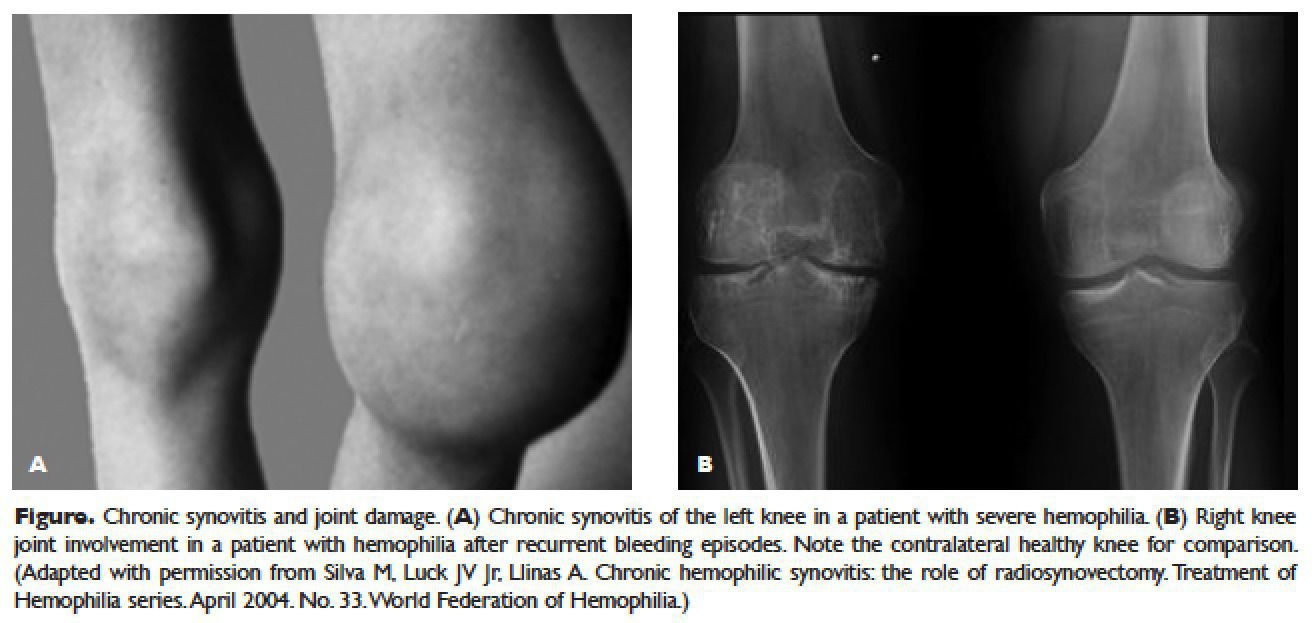

The most common congenital coagulation factor deficiency is caused by reduction in the amount or activity of factor VIII. It is X linked recessive so it is only found in males while females are only asymptomatic carriers. Hemophilia B (Christmas disease) is caused by factor IX deficiency. Classification: 1. Severe = less than 1% of normal factor VIII deficiency 2. Moderate = 2-5% of normal factor VIII activity. 3. Mild = 6-50% of normal factor VIII activity. Certain clinical findings are seen suh as spontaneous hemorrages (eg: gastrointestinal), hemarthrosis i.e. bleeding in joints, muscle hematomas especially in calf and psoas muscles. Petechia are classically absent. Lab findings are increased PTT while normal PT and platelets count. Mild cases are managed through Desmopressin while severe cases require recombinant factor VIII therapy. Image from mdedge.com